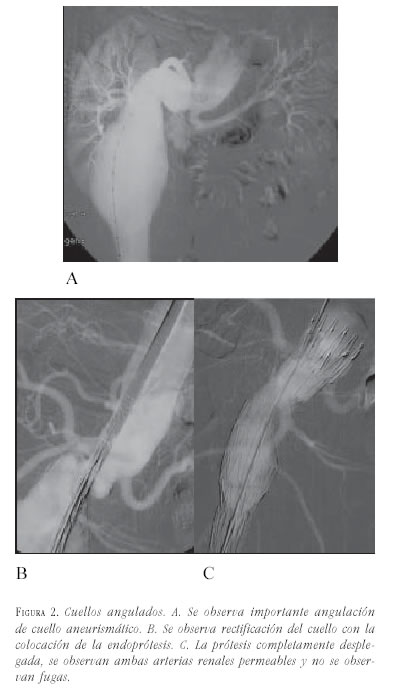

- Angulación: se define como el ángulo formado entre el cuello aórtico proximal y el eje longitudinal principal del aneurisma. El eje del aneurisma se define como la línea que va desde la porción proximal del aneurisma, o extremo distal del cuello proximal, hasta la bifurcación ilíaca. Se clasifica en leve cuando va de 0 a 30°, moderada cuando es de 30-60°, y severa cuando es mayor de 60°. La angulación del cuello proximal puede ser perjudicial cuando supera los 50° y cuando es mayor de 60°, generalmente se considera una contraindicación relativa para el tratamiento endovascular. El Cómite Endoluminal de la Sociedad de Cirugía Vascular / Sociedad Internacional de Cirugía Cardiovascular recomienda angulaciones máximas en el cuello de 120 grados (figura 2).

Los cuellos angulados deberán ser sometidos a una serie de pruebas para conocer su comportamiento, mediante la colocación de las guías rígidas y/o introductores para estimar su corrección.

Se recomienda el uso de prótesis de fácil desplazamiento y con fijación suprarrenal. En estos casos es conveniente que el cuello tenga una longitud superior a los 15 mm, porque sin duda se perderá parte del mismo durante las maniobras de soltura al hacerlo de forma asimétrica.

También es muy importante controlar la posición de las arterias renales, porque en estos casos es dificil de visualizar su origen correcto. En general los cuellos tienen dos desplazamientos: anterior o lateral; éstos últimos son más fácilmente corregibles.